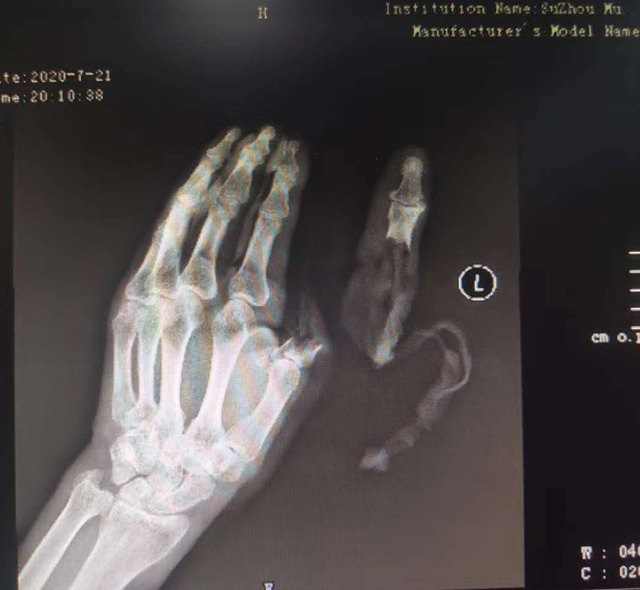

△老人送醫(yī)時(shí)的手部狀態(tài) 蘇州市立醫(yī)院供圖

現(xiàn)代快報(bào)記者了解到,7月21日下午,這名76歲的老人在家擦拭面粉機(jī)時(shí),忘記關(guān)閉電源,結(jié)果抹布被纏進(jìn)機(jī)器,順帶著將老人的手也帶進(jìn)機(jī)器中。老人奮力掙脫,可為時(shí)已晚,待將手取出時(shí),已經(jīng)血肉模糊,大拇指在脫落后還被絞入機(jī)器軋了一圈……